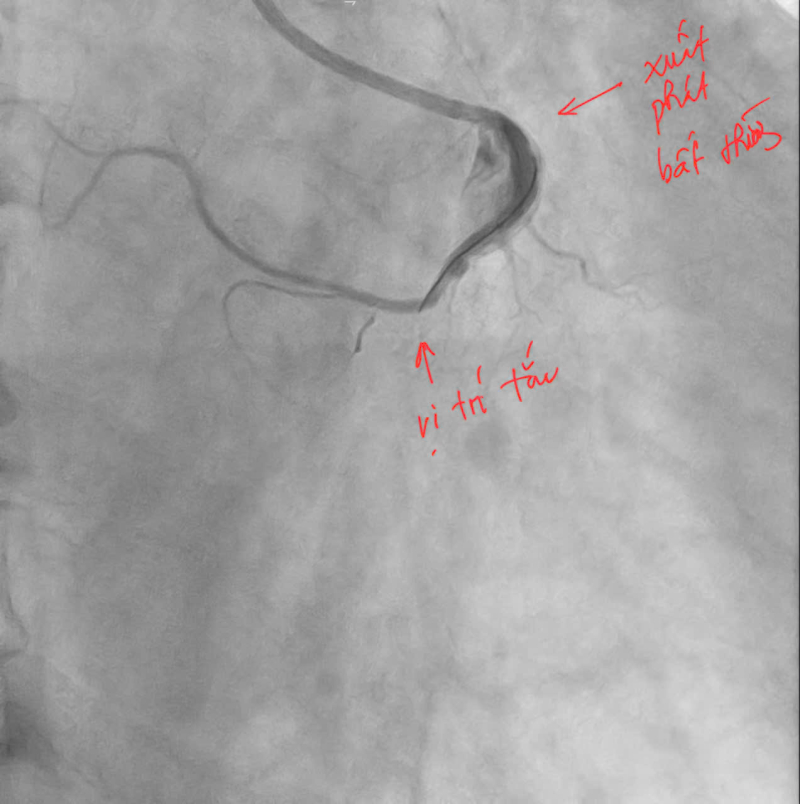

Ngay lập tức, bệnh nhân được kích hoạt quy trình cấp cứu tim mạch và chuyển tới phòng can thiệp mạch vành khẩn cấp. Kết quả chụp mạch vành cho thấy bệnh nhân bị tắc hoàn toàn động mạch vành phải đoạn 2 (RCA 2). Đáng chú ý, động mạch vành phải của bệnh nhân có vị trí xuất phát bất thường từ xoang vành trái của động mạch chủ – một dạng dị dạng hiếm gặp khiến việc tiếp cận và can thiệp trở nên phức tạp hơn nhiều so với các trường hợp thông thường.

Hình ảnh: Trước can thiệp